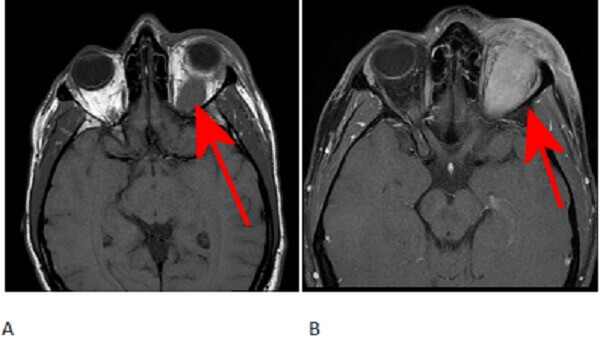

Figure 1: Red arrow. T1 pre (A) and post (B) contrast images demonstrate an ovoid T1 hypointense homogenously enhancing mass involving the superior lateral retro-orbital space with surrounding fat stranding as seen on the T2 fat saturated coronal images (C) . The mass is separate from the optic nerve (green arrow) but difficult to separate from the superior rectus.

However, it can be pleomorphic (like this case), can involve any part of the orbit and is often T1 hypointense and enhancing. Orbital pseudotumor can be difficult to distinguish from lymphoma, although the latter is typically bilateral. Unlike thyroid ophthalmopathy, pseudotumor does not spare the tendinous insertions of the extra-ocular muscles. Pseudotumor typically responds well to steroids. Atypical features or poor steroid response may require biopsy to exclude other etiologies.